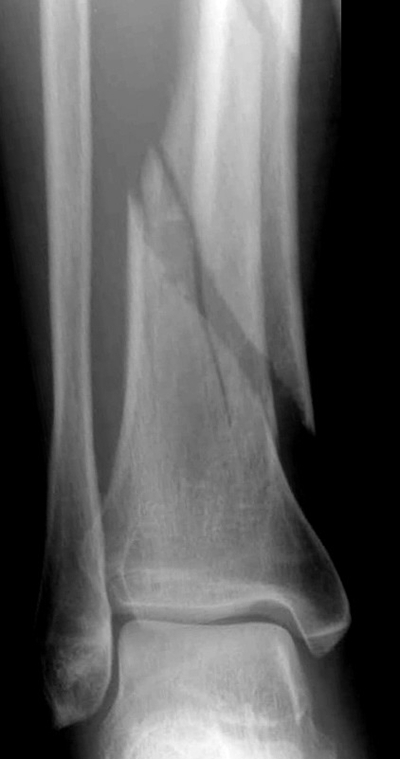

骨折圖片